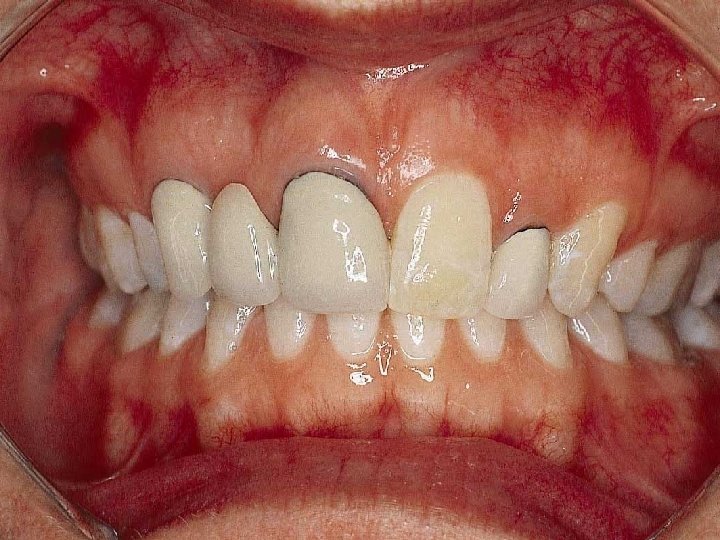

Cementation Procedure 1. Remove temporary and all residue of temporary cement 2. Check occlusion on adjacent teeth (mylar shimstock and articulating paper) 3. Place rubber dam 4. Clean tooth with pumice and rubber cup, rinse and lightly dry 5. Try in restoration for fit.

6. Adjust proximal contacts if necessary 7. Evaluate shade intraorally using water soluble try-in paste (optional) 8. Rinse out try-in paste and air dry 9. Etch inside of restoration (HF porcelain etchant X 2 minutes), rinse with distilled water and air dry 10. Place drop of silane (porcelain primer) on intaglio surface for 1 minute, lightly air thin to evaporate solvent